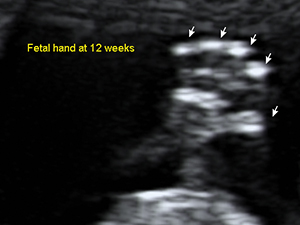

First Trimester

Fetal hand at 12 weeks